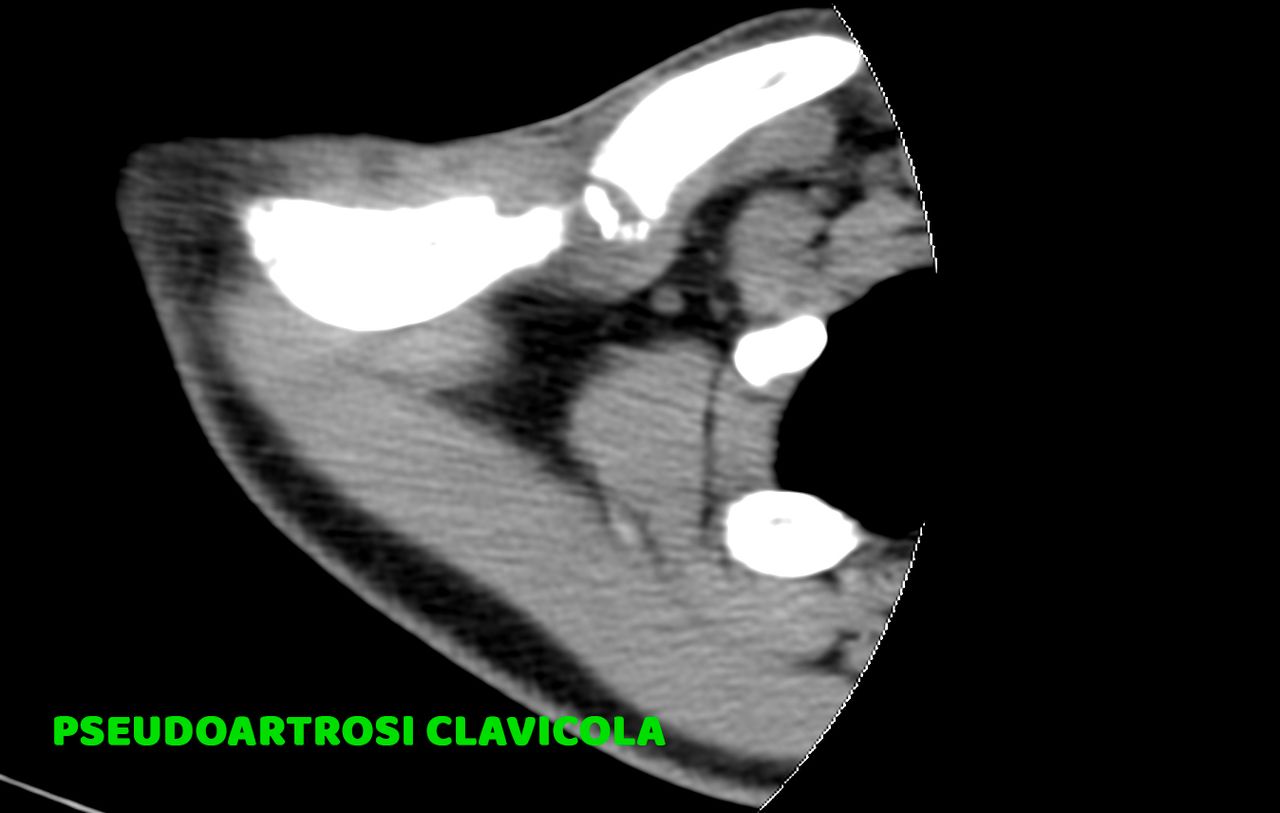

CHIRURGIA DELLA MANO:

* Neurolisi (Sindrome del Tunnel Carpale), Tenolisi (Dito a scatto, Sindrome di De Quervain), Morbo di Dupuytren

(trattamento percutaneo)

* Protesi della Trapezio Metacarpica (Rizoartrosi)